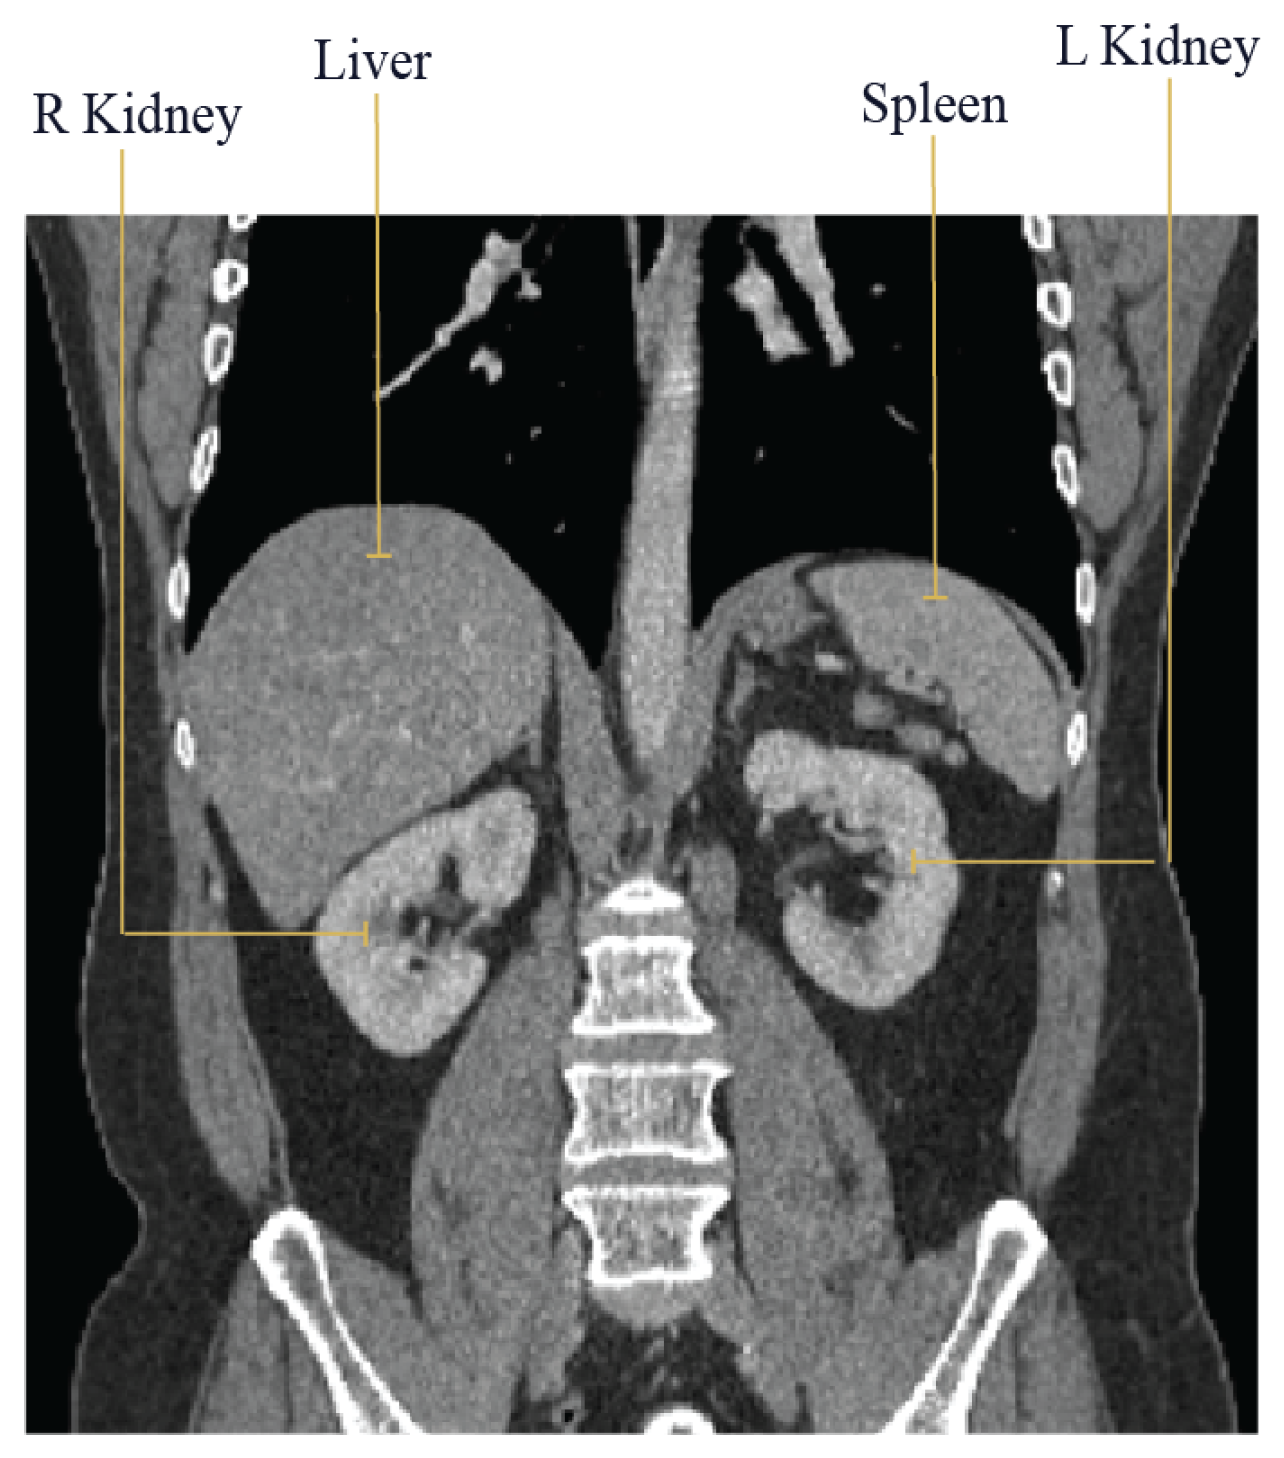

5.1. Datasets

5.1.2. Hospital Dataset